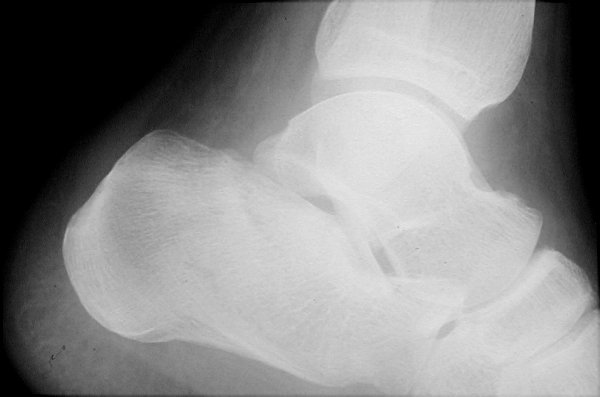

Return to Calcaneus Fracture